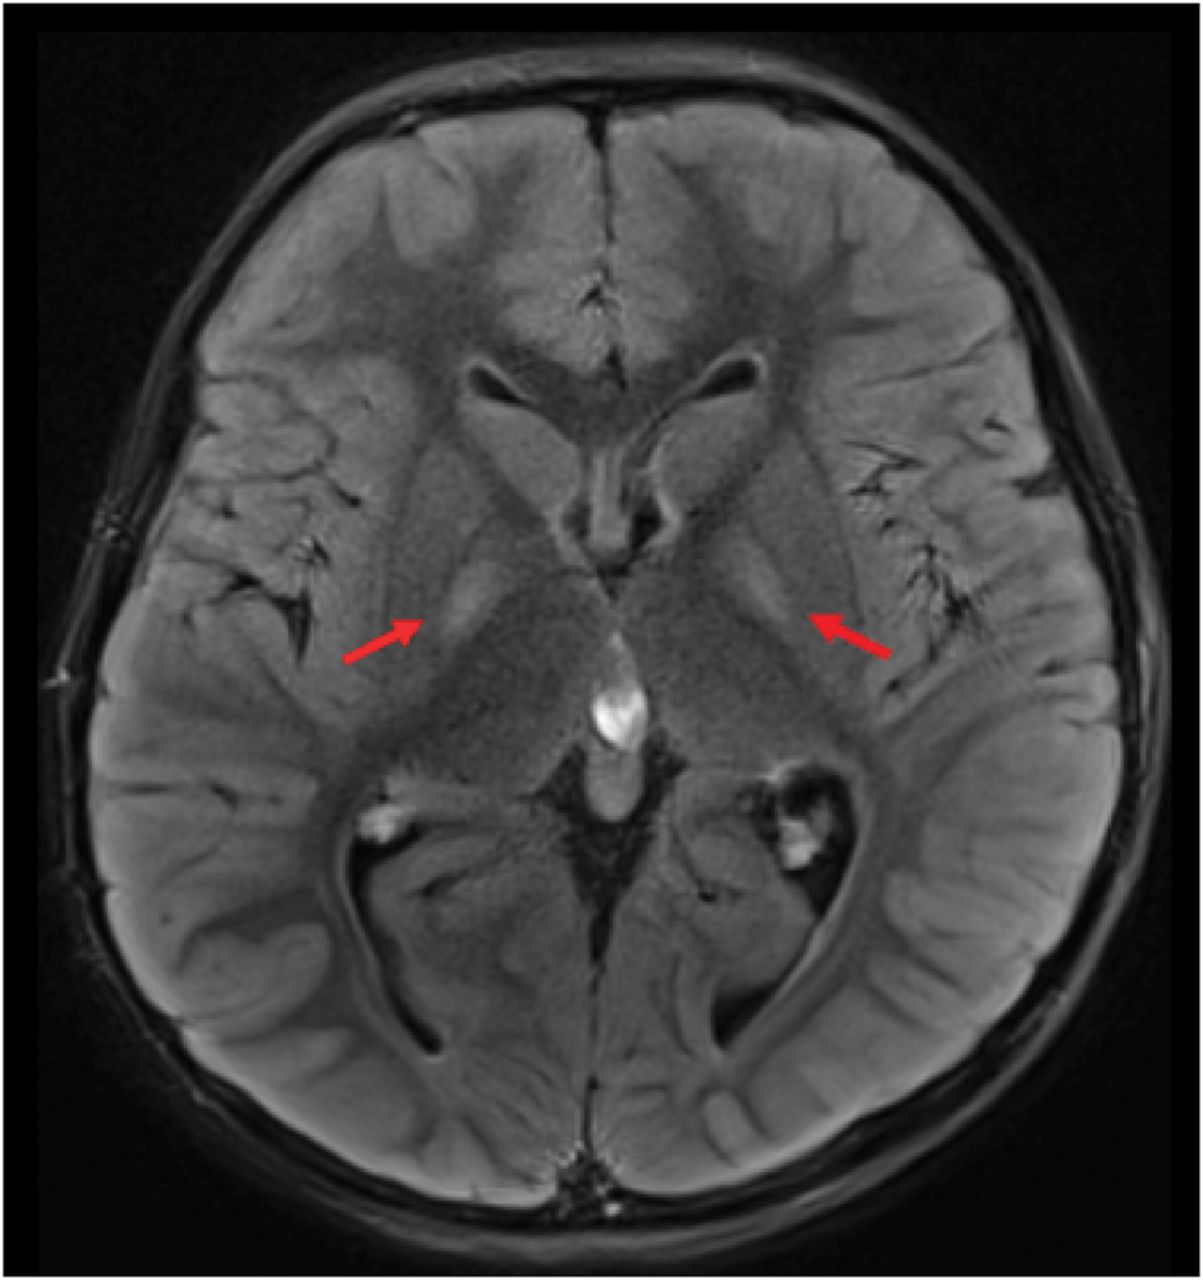

考试,他是一个营养良好的男孩,适龄的语言、电机、和社交技巧。姿势和上肢动力学震颤,无需测距不准或步态共济失调。剩余的神经系统检查是正常的。没有矛盾的事件引发了在考试期间或之后短暂的运动。家族史是著名的兄弟姐妹孤独症和多动症;母亲发作二次脑震荡。实验室调查显示海拔血清丙酮酸(0.221更易/ L)。CSF葡萄糖低在48 mg / dL, CSF乳酸(4.3更易/ L)和丙氨酸(59.2 mcmol / L)升高;完整的实验室数据详细eTable 1 (links.lww.com/WNL/C656)。大脑MRI是著名的双边pallidal hyperintensities (图1)。

这个案例说明了几个陷阱在调查的上下文中PED怀疑GLUT1-DS患者。首先,成像异常并不GLUT1-DS一般。更改兼容Leigh-like综合症(对称T2 /天赋hyperintense基底神经节和/或脑干病变),如中描述图1可以看到,在丙酮酸脱氢酶缺乏症和线粒体疾病。

PDH情结是一种酶组装不同的亚基编码的PDHA1,PDHB,DLAT,PDHX,‘基因。在84%的情况下,缺陷是由突变引起的PDHA1基因,X-linked-although女性可能存在疾病取决于X失活的模式。临床上,PDH不足影响主要是中枢神经系统发现先天性头小畸型,肌张力减退、癫痫、共济失调和可变程度的发育迟缓。虽然可能会有一些临床重叠,4先前确定临床表型亚型:阵发性运动症状和发育迟缓;情景性共济失调与周围神经病变;急性脑干和基底神经节功能障碍与“Leigh-Like MRI和脑病新生儿乳酸酸中毒,面部先天性畸形、脑畸形。7然而,PDH障碍的临床表现是扩大与下一代测序。大脑MRI显示胼胝体发育不全,和双边基底神经节有或没有脑干T2 hyperintensities,暗示Leigh-like模式。代谢异常如增加等离子体丙酮酸、乳酸酸血症,CSF乳酸增加,可以出现代谢性酸中毒。6,7